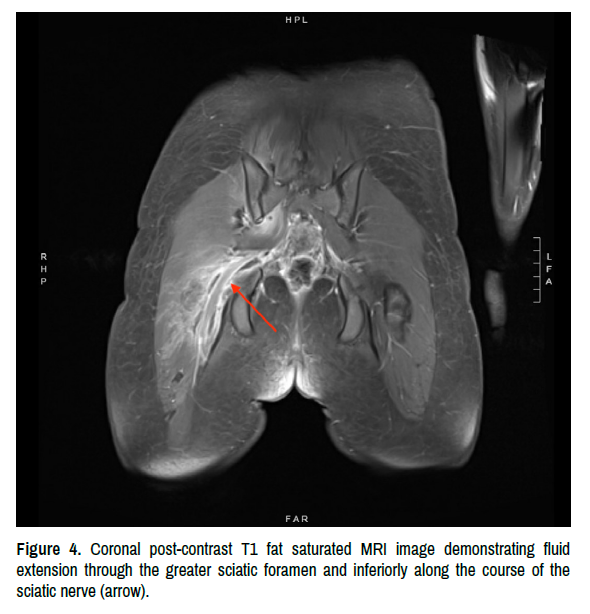

After transfer, additional imaging with abdominal ultrasound redemonstrated a normal appendix, non-specific inflammatory changes in the RLQ, a small amount of free fluid, and mild wall thickening of the terminal ileum. No joint effusion in the right hip was noted. Orthopedics was consulted for the concern of a septic hip, which they believed was very unlikely so they decided not to perform an arthrocentesis. The decision was made to obtain an MRI of the pelvis with IV contrast. It demonstrated an extensive loculated fluid collection concerning for an abscess along the right pelvic sidewall, extending into the right piriformis muscle, and tracking inferiorly along the right sciatic nerve (Figures 3 and 4).

clinical-case-reports-sciatic

Figure 4. Coronal post-contrast T1 fat saturated MRI image demonstrating fluid extension through the greater sciatic foramen and inferiorly along the course of the sciatic nerve (arrow).

Plain radiographs, CT of the abdomen and pelvis, and abdominal ultrasound all failed to confirm the diagnosis, and ultimately the abscess was found on MRI. Its extension into the piriformis muscle, one of the short external rotators of the hip, explains why she was able to tolerate flexion but not internal/external rotation of the hip. The Kocher Criteria are relatively nonspecific, and if present they signal an acute infection or inflammation, but they are not specific to intra-articular pathology such as septic arthritis.